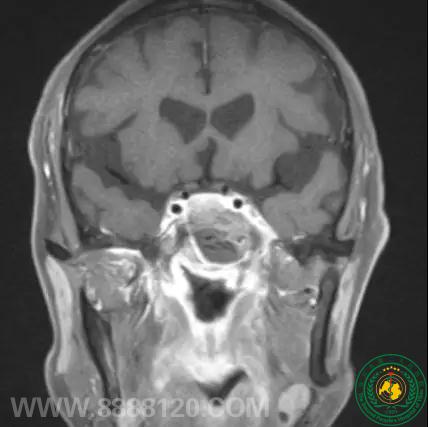

术后图像

术后病检提示为脑膜瘤(WHO-I级)

蝶窦脑膜瘤属于异位脑膜瘤罕见病例,查阅文献资料全国仅报道一例我院神外一科完成的该例手术属于全省第一例而且经鼻神经内镜下完整切除肿瘤,体现了我院神经内镜技术又上一个台阶。